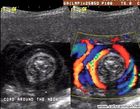

Gebelik, insan yaşamında beslenmenin en önemli olduğu devrelerden biridir. Gebelik dönemindeki beslenme şekli anne ve doğacak bebeğin sağlığını büyük ölçüde etkiler. Bu demek değildir ki, anne adayları iki canlıdır, iki kişilik yiyecek. Gebelikte gereğinden fazla beslenme de eksik beslenme kadar bebek ve anne sağlığına zararlıdır. Kordon Dolanması, sanılanın aksine korkulacak bir durum değildir. Hekiminiz böyle bir durumla karşılaştığında sizi aydınlatacaktır.Gebeliklerde anne adaylarının en korktuğu şey bebeğin boynuna kordon dolanmasıdır.Gebeliklerin % 25-30'unda görülen bu durum her zaman ciddi sorunlara yol açmaz.Göbek bağı, kordon içindeki damarları koruyan yumuşak,jelatinimsi madde ile kaplıdır.

Kordon Dolanması, sanılanın aksine korkulacak bir durum değildir. Hekiminiz böyle bir durumla karşılaştığında sizi aydınlatacaktır.Gebeliklerde anne adaylarının en korktuğu şey bebeğin boynuna kordon dolanmasıdır.Gebeliklerin % 25-30'unda görülen bu durum her zaman ciddi sorunlara yol açmaz.Göbek bağı, kordon içindeki damarları koruyan yumuşak,jelatinimsi madde ile kaplıdır. açısından, aile planlaması büyük bir önem taşıyor. Kendilerini hazır hissettikleri zaman diliminde, arzuladıkları sayıda çocuk sahibi olabilmeleri için aile planlaması gerekir. İstenmeyen gebelilerin sonlandırılması durumunda annenin psikolojisi zarar görür. Hekim olarak istenmeyen gebeliği olmadan önlemek ilk amacımızdır.